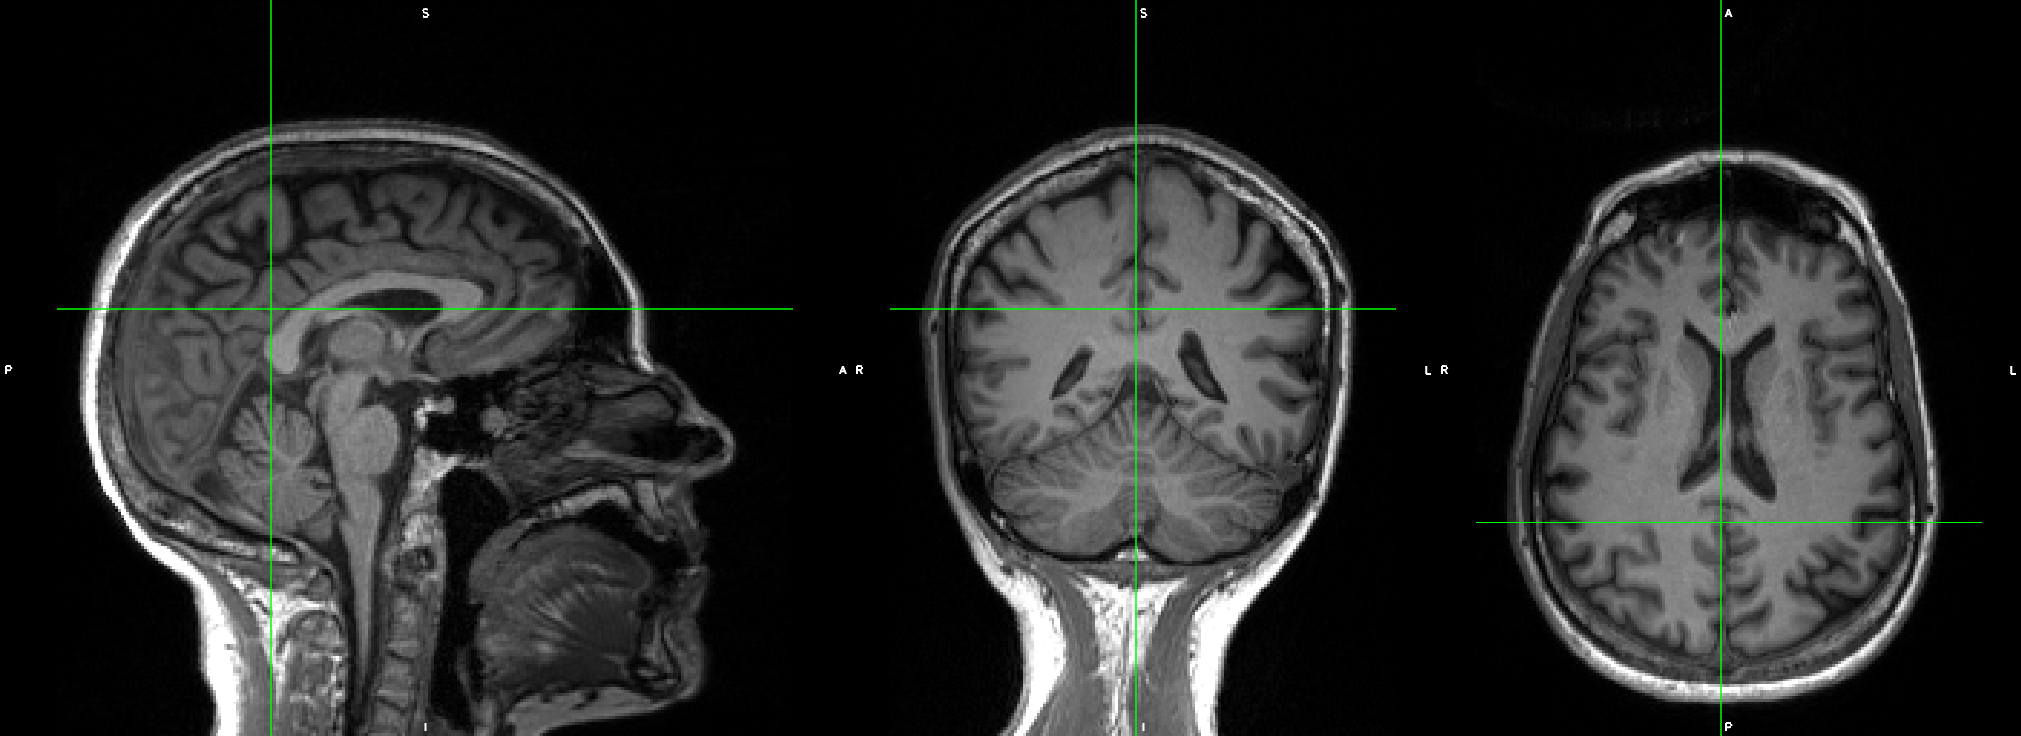

The original T1w image looked perfect, with no artifact, no head motion. But in the _desc-preproc_T1w.nii.gz, the image looked like it had two brains overlapping.

This is the raw T1w image